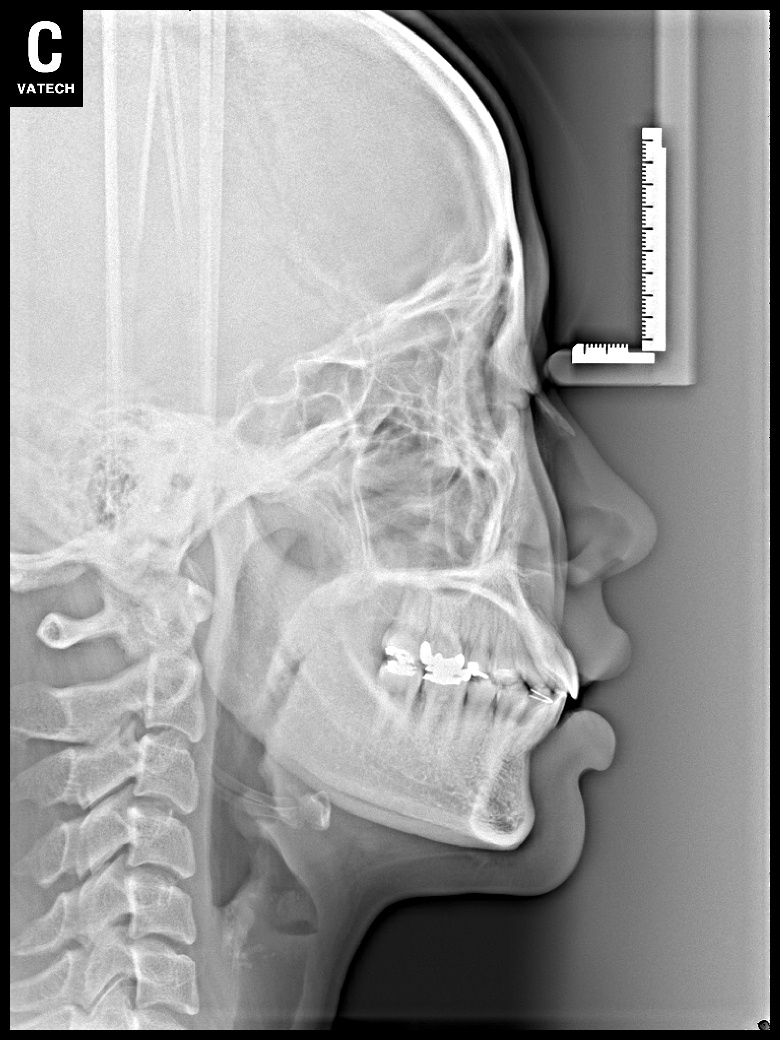

치료 후 사진입니다.